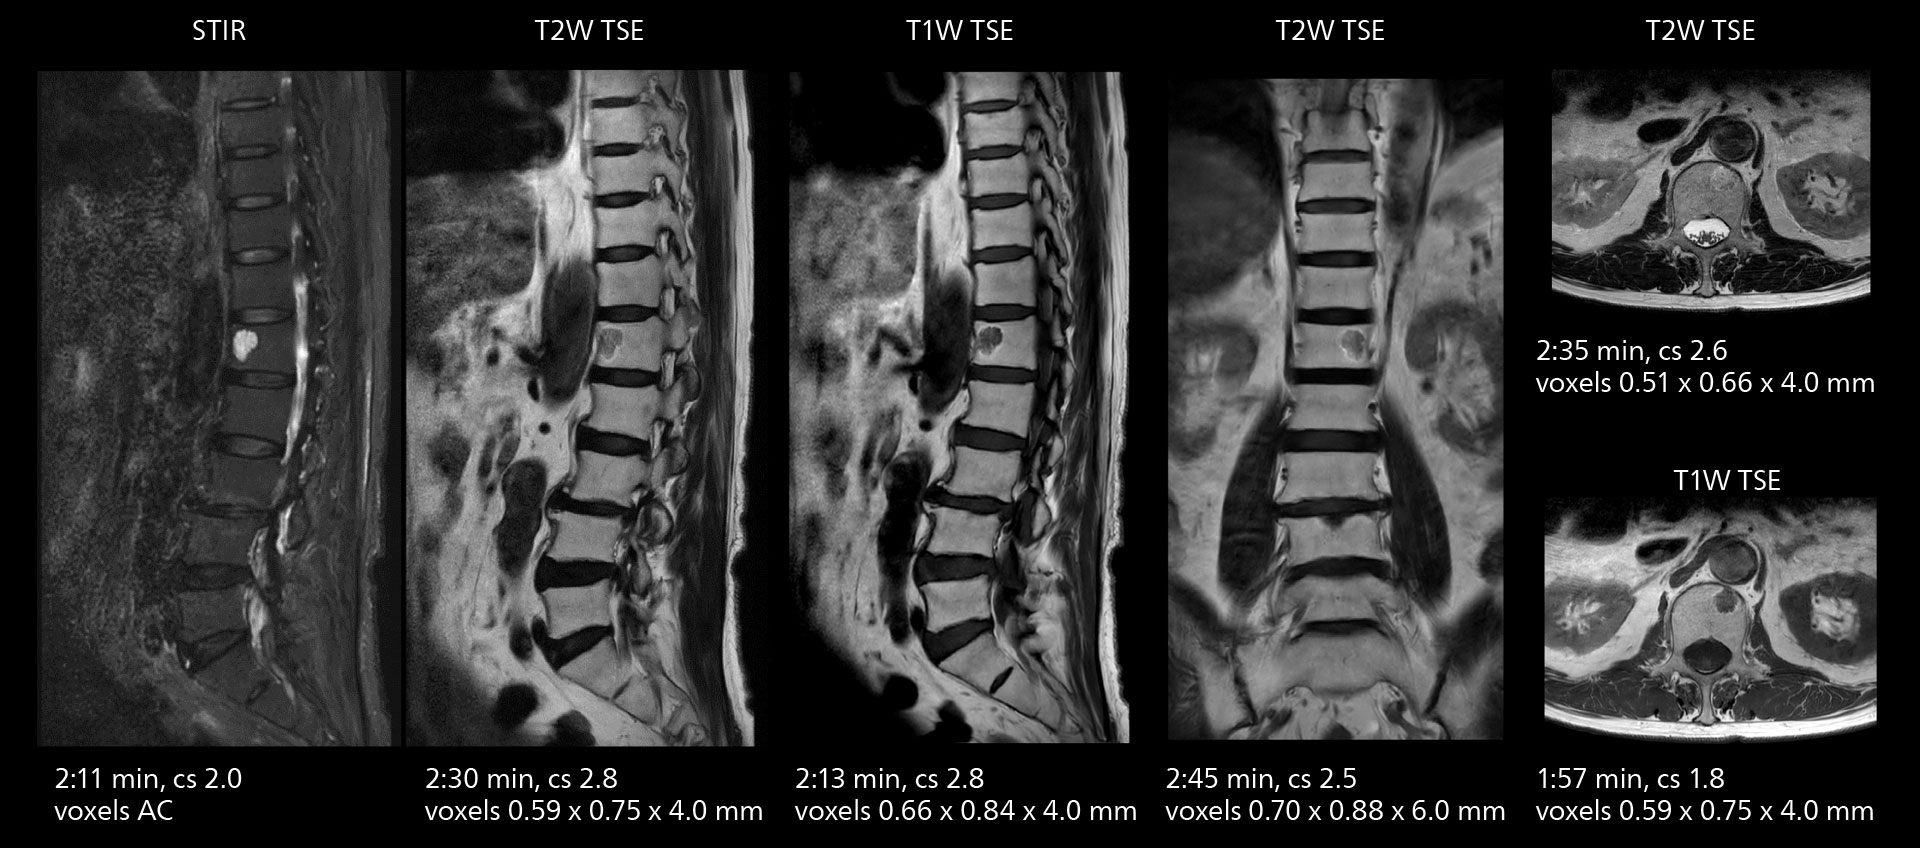

With SmartPath to Elition X the team can obtain excellent quality DWIBS imaging and reduce imaging time. Other sequences also fit in the examination slot. This case shows left paravertebral neurogenic tumor and Th10 vertebral hemangiomas.